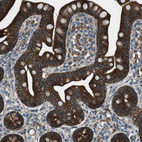

Immunohistochemical staining of human pancreas shows strong membranous and cytoplasmic positivity in exocrine glandular cells.